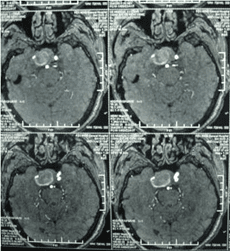

頸內(nèi)動脈虹吸段巨大動脈瘤(約3cm ×3cm)

顱內(nèi)動脈瘤是指腦動脈的局部性異常擴(kuò)大,多在腦底動脈的分叉處或分支的夾角向外突出,多呈囊狀。TCD對顱內(nèi)動脈瘤的總檢出率為67 %,動脈瘤>1cm的檢出率為82 %。TC D 對較大動脈瘤的檢測有其特征性表現(xiàn),其典型表現(xiàn)為:瘤體內(nèi)血流速度明顯低于載瘤動脈血流速度,其收縮峰陡峭或多峰不整,舒張期末流速極低或斷流,PI 值增高,多為雙向血流,聲頻低鈍,似撞擊樣轟鳴音。